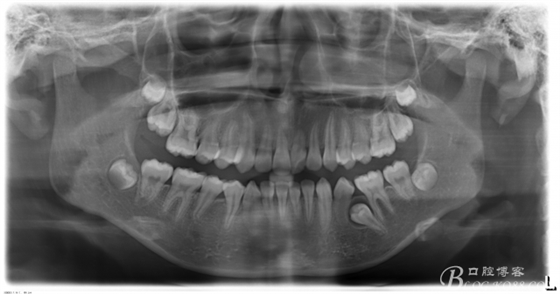

圖1. 左側(cè)35阻生、牙冠周圍牙囊影明顯,疑為35含牙囊腫。